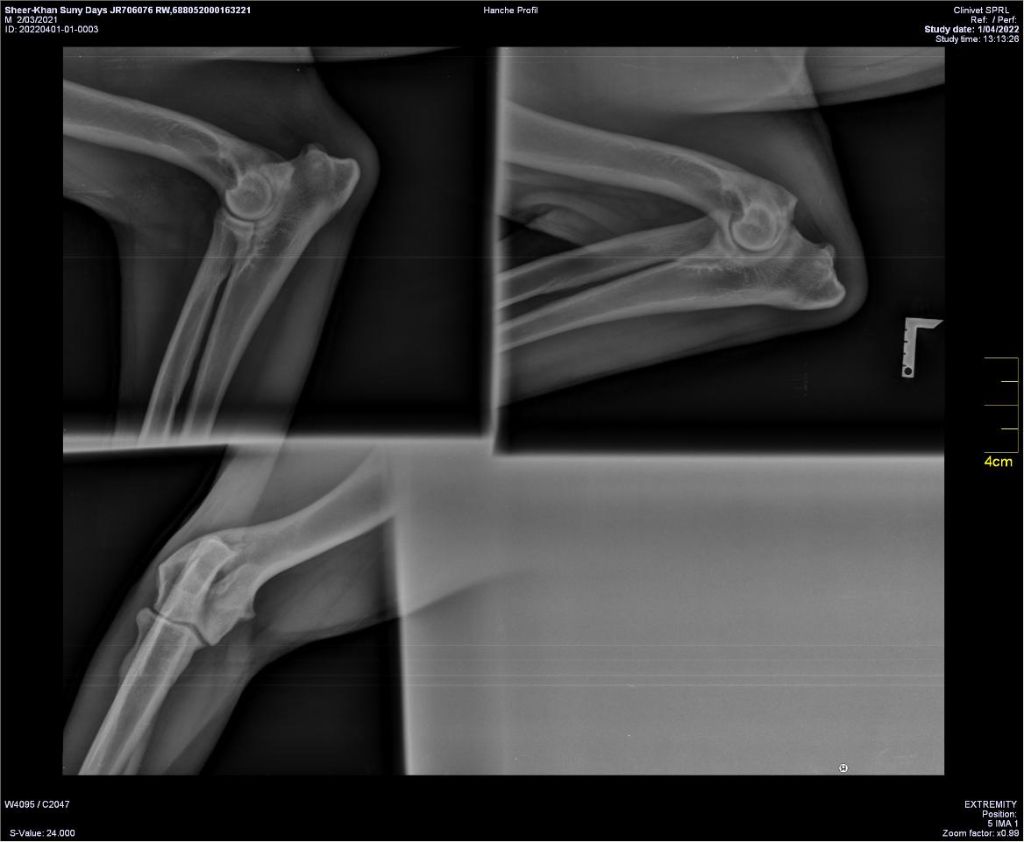

COUDES

Lecture officielle coudes